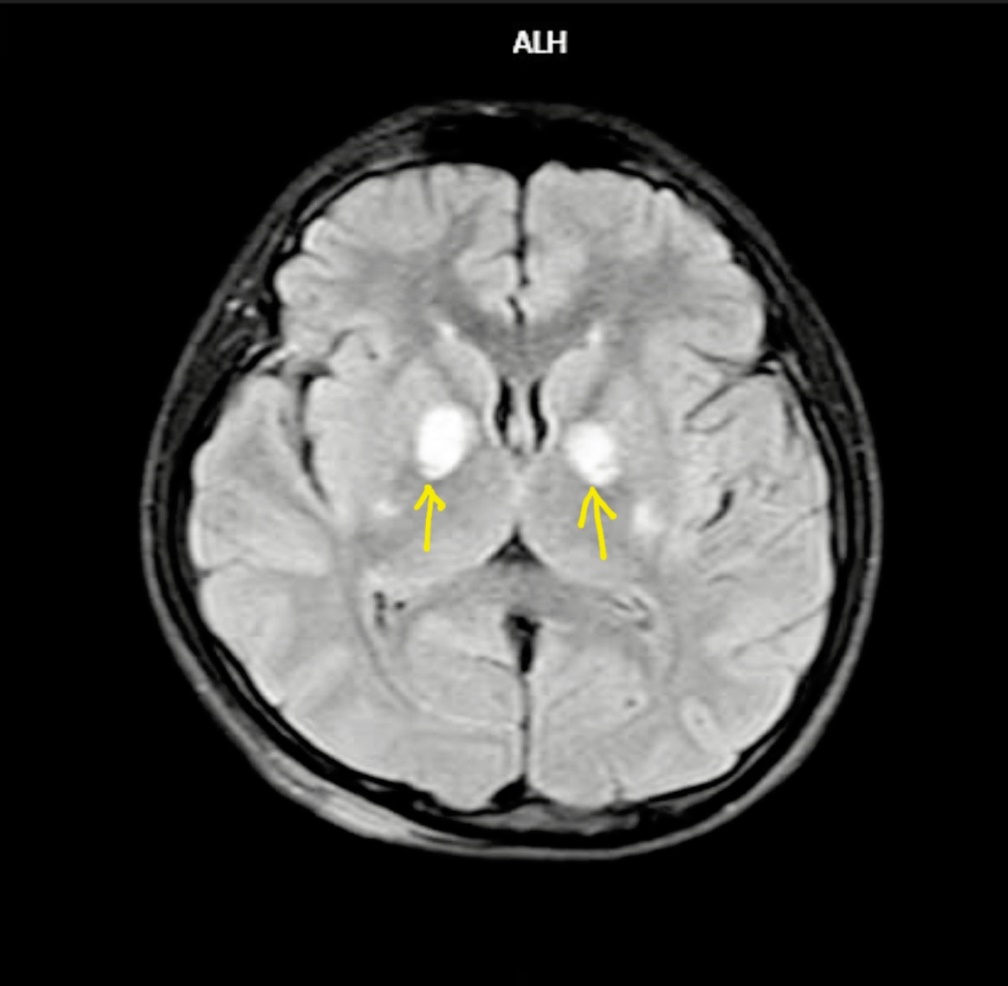

Não bệnh nhân 15 tuổi bị tổn thương do ngộ độc khí CO,qua hình ảnh chụp chiếu. Ảnh: Nguyên Hà

"Cả hai mẹ con có tổn thương rõ trên não nên nguy cơ cao sau này gặp các di chứng muộn",bác sĩ Thuận nói,thêm rằng bệnh nhân cần theo dõi,điều trị rất cẩn thận. Bác sĩ cũng khuyến cáo người chồng dù ra viện vẫn phải theo dõi sát và kiểm tra sức khỏe để tránh di chứng muộn.